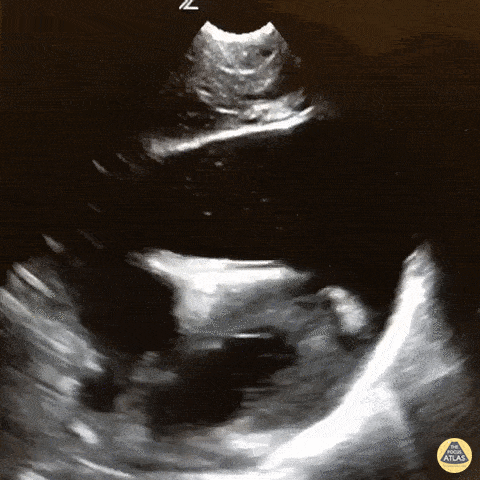

WCUME 2017 Submission for "Best POCUS" Massive hemopericardium with coagulating blood and tamponade in a pediatric trauma patient. The patient went straight to the OR based on this image! Dr. Sarah Medeiros - Sacramento, CA